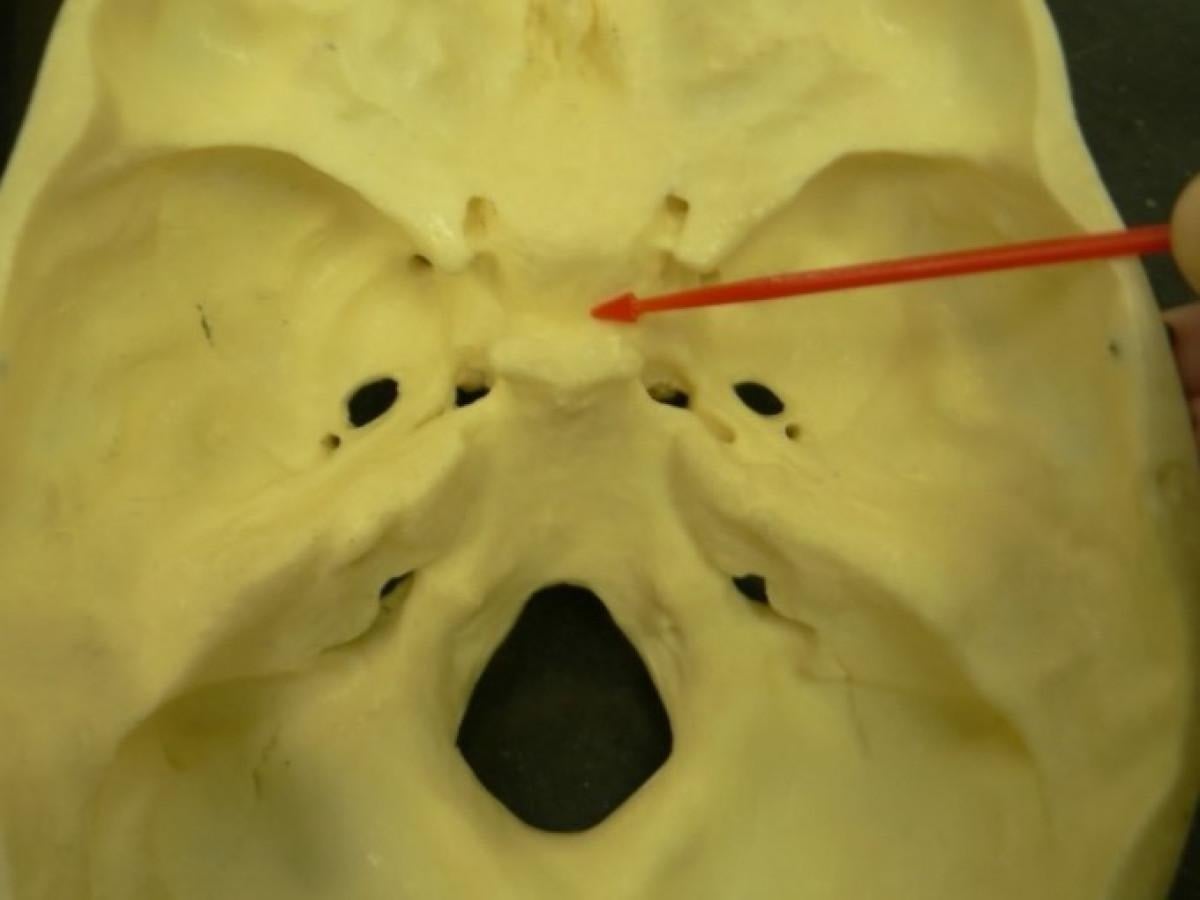

Anatomide "Sella turcica" olarak geçen ve halk arasında "Türk Eyeri" olarak bilinen kemik, vücudun önemli bir yapısıdır.

Bu kemik, kafatasının alt kısmında, gözlerin arkasında yer alır ve şekli, eski Türk atları için kullanılan eyere benzetildiği için bu adla anılır.